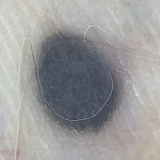

Внешне голубой невус Ядассона–Тиче представляет собой небольшого размера (до 8–10 мм в диаметре) плоскую или слегка приподнятую над кожей родинку. Поверхность такой родинки гладкая, без явной бугристости. Цвет может варьировать от голубого до тёмно-синего, причем окраска неравномерная из-за достаточно глубокого залегания образующих опухоль меланоцитов. В некоторых случаях размер невуса больше стандартного — до 3–3,5 см. Контур невуса не всегда четкий. Форма бывает круглая, вытянутая или веретенообразная. Ни равномерность окраса, ни форма родинки не является указателем на необходимость удаления или отсутствие такой потребности.

При классификации голубого невуса в современной медицине принято выделять вульгарную (неклеточную, простую), клеточную и комбинированную формы голубого невуса. Комбинированные голубые невусы сочетают в себе признаки клеточной и простой формы. Независимо от типа риск малигнизации такого невуса неизменно низкий.

Неклеточный (простой) голубой невус выглядит как эластичный узелок, похожий на мелкое инородное тело под кожей. Диаметр темного плотного узелка обычно 6-8 мм. Цвет — от серого с голубым до насыщенного чёрного. Чаще всего вульгарный неклеточный невус обнаруживают на шее, лице, тыльной стороне ладоней и стоп. Также он может вырастать и на слизистой рта и половых органах, встречается голубой невус на губе и волосистой части головы, что может затруднять его своевременное обнаружение.

Клеточная форма отличается от неклеточной размерами — родинки такого типа в диаметре не менее полутора сантиметров. Из-за неоднородной по насыщенности окраски и часто встречающейся бугристой «рыхлой» поверхности его можно принять за меланому, формы которой могут иметь схожий набор признаков. Наиболее часто встречающиеся места локализации такого невуса — поясница и ягодицы, реже — кисти и стопы.